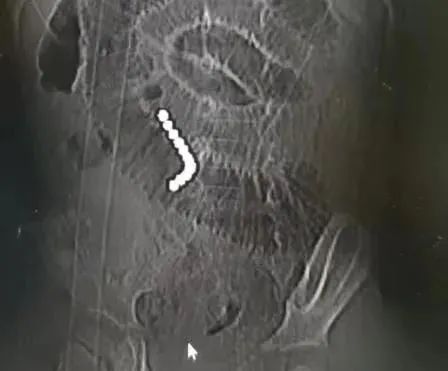

小杰今年3岁,9月1日早上刚上幼儿园的他称肚子有点疼,以为孩子是害怕上学,父母和老师都没太在意。然而到了下午,腹痛加重,父母赶紧带孩子到东莞当地医院就诊,进行了药物治疗,但并没有改善症状,疼痛的频率以及程度都在不断加重。第二天进行腹部X线检查,才发现孩子腹腔内有一串连在一起的异物。考虑到情况严重,小杰9月3日凌晨被转入珠江医院小儿外科。“当时患儿腹痛腹胀的症状依然很明显,腹部影像检查结果很清晰,腹腔内足足有11颗并排的珠子”,小儿外科主任杨六成教授表示。

父母这才想起来,半个月前,确实有朋友给孩子买了磁力珠玩儿。“当处在不同肠管中的磁力珠合并在一起,强大的磁力吸引会夹挤肠管,被压住的肠管会逐渐缺血、坏死,最后穿孔。一旦穿孔后的肠内容物溢出至腹膜腔,可能会引起弥漫性腹膜炎,除了剧烈腹痛、腹胀等症状,严重的会导致休克甚至死亡。”医生表示,现在孩子体内有11颗磁力珠,具体穿孔情况不得而知,孩子腹痛情况又不断加剧,需要立即急诊手术。手术中发现,11颗磁力珠分别位于3段不同的肠管,已经导致了4处肠管穿孔。通过腹部一个小切口取出11颗磁力珠后,医生团队立即切除缝合了两个贯穿样穿孔的肠管,修补了另两处穿孔的肠管。为防止缝合的肠管出现感染,术后进行了相应的治疗与精心护理,术后第9天,小杰终于可以开始吃东西了,9月15日顺利康复出院。